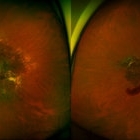

"Flower" Macular Degeneration (Wet)

Jul 13 2013 by Jason S. Calhoun

Patient with (wet) macular degeneration in the left eye. Notice the "flower" shape abnormal blood vessels staining.

Photographer: Jason S. Calhoun, Department of Ophthalmology, Mayo Clinic Jacksonville, Florida

Imaging device: TOPCON TRC 50-EX

Condition/keywords: choroidal neovascularization (CNV)